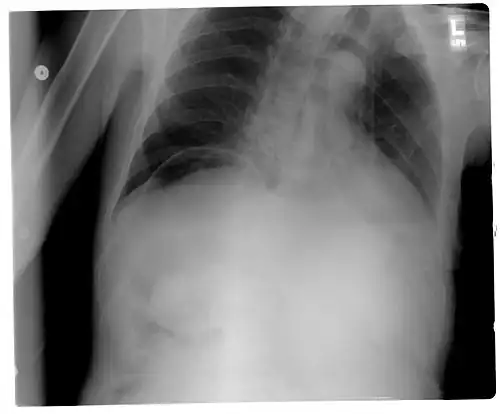

| Frontal chest X-ray. The air bubble below the right hemidiaphragm (on the left of the image) is a pneumoperitoneum. | |

When present, pneumoperitoneum can be seen on projectional radiography, but small amounts are often missed, and CT scan is nowadays regarded as a criterion standard in the assessment of a pneumoperitoneum.[18] CT can visualize quantities as small as 5 cm3 of air or gas.

Signs that can be seen on projectional radiography are shown below:

As differential diagnoses, a subphrenic abscess, bowel interposed between diaphragm and liver (Chilaiditi syndrome), and linear atelectasis at the base of the lungs can simulate free air under the diaphragm on a chest X-ray.